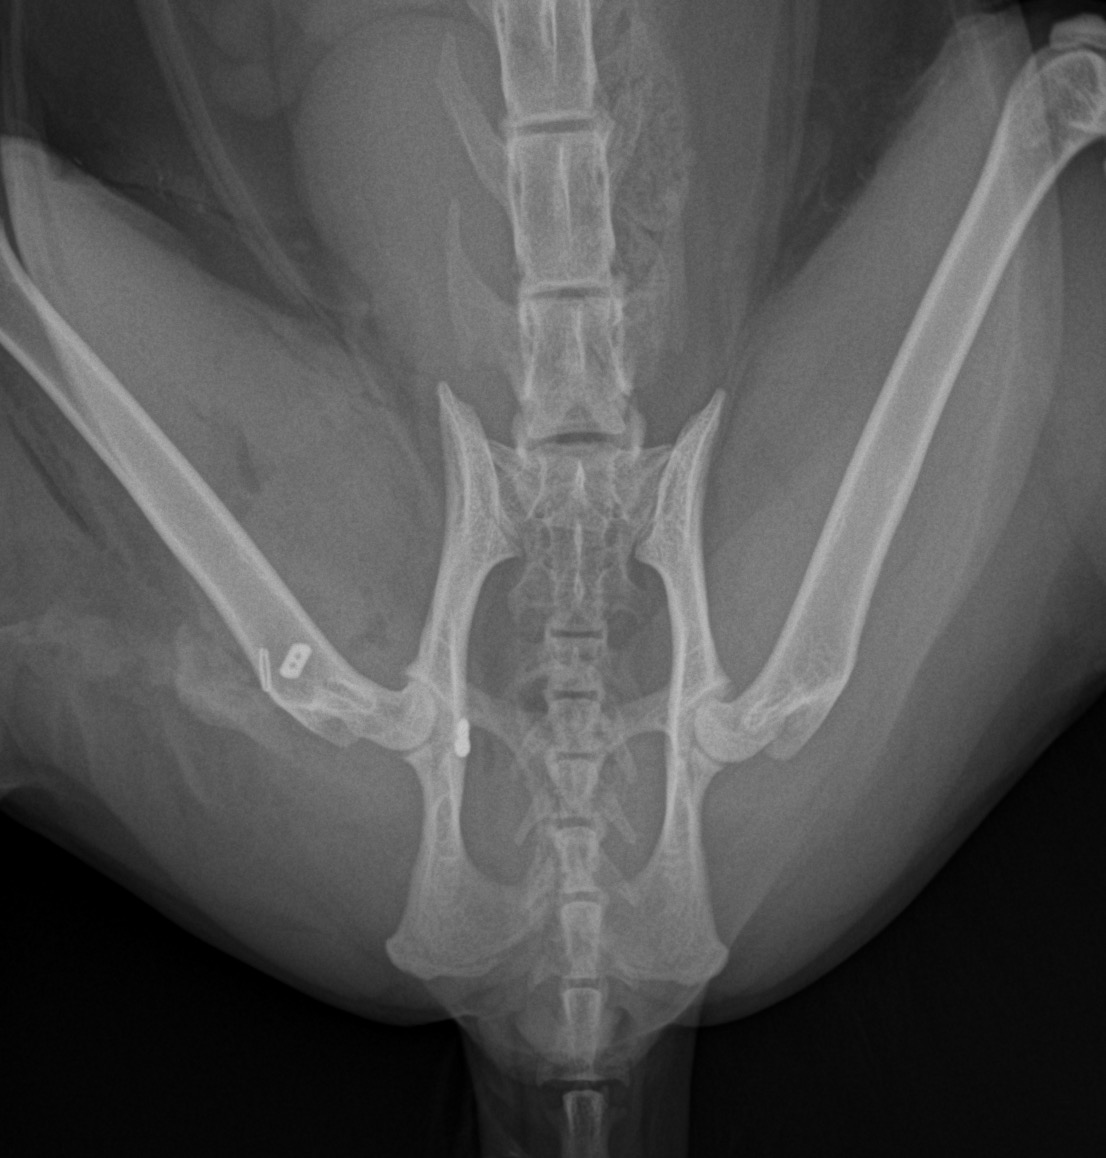

猫の股関節脱臼 外出から帰宅すると猫ちゃんが右後肢を跛行しているとのことで、救急で来院されました。エックス線では右股関節の背側前方脱臼が確認されました。トグルピンと人工靱帯により脱臼した大腿骨を寛骨内に整復します。しばらく安静が必要となります。 症例カテゴリー 放射線治療整形外科軟部組織外科脳神経外科内科腫瘍外科救急・集中治療リハビリテーション科腫瘍内科内視鏡科脳神経科呼吸器外科中医・漢方猫の腎移植循環器科